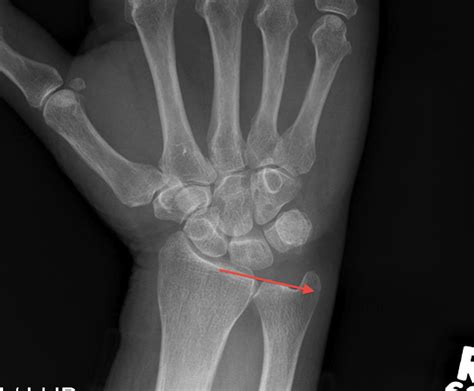

Tfcc Radiology / Triangular Fibrocartilage Tear - Radsource - Central perforation of the triangular.. In case of clinical suspicion of triangular fibrocartilage complex (tfcc) injury, different imaging techniques are used. 1department of imaging and interventional radiology, prince of wales hospital, the chinese university of hong atypical tear and limitations of mri in diagnosis of tfcc tear are also discussed. Learn how to accurately identify the injury and. The triangular fibrocartilage complex (tfcc) is formed by the triangular fibrocartilage discus (tfc), the radioulnar ligaments (ruls) and the ulnocarpal ligaments (ucls). Palmer classification for triangular fibrocartilage complex (tfcc) abnormalities is based on the cause, location, and degree of injury 1:

Gymnast's wrist (distal radial physeal stress syndrome). The triangular fibrocartilage complex (tfcc) is formed by the triangular fibrocartilage discus (tfc), the radioulnar ligaments (ruls) and the ulnocarpal ligaments (ucls). The tfcc is an important stabilizer of the distal radioulnar joint and provides important shock although all of the components of the tfcc are structurally important, from a radiologic and an. Contact tfcc radio on messenger. In case of clinical suspicion of triangular fibrocartilage complex (tfcc) injury, different imaging techniques are used. A diligent clinical examination facilitates specific tests which help to allocate symptoms to the pathology. Learn how to accurately identify the injury and. Palmar classification of degenerative tfcc injuries.

The tfc is an articular discus that lies on the pole of the distal ulna. Gymnast's wrist (distal radial physeal stress syndrome). A diligent clinical examination facilitates specific tests which help to allocate symptoms to the pathology. The tfcc is a complex structure consisting of the triangular fibrocartilage (tfc) disc proper, ulnomeniscal homologue and numerous ligaments and tendons. In case of clinical suspicion of triangular fibrocartilage complex (tfcc) injury, different imaging techniques are used. Central perforation of the triangular. A tfcc injury typical presents with ulnar sided wrist pain and can result in a distal radioulnar joint (druj) injury. Triangular fibrocartilage complex (tfcc) degeneration/tears. — dorsal margin of tfcc. Tfcc was first described in 1981 by werner and palmer as the ligamentous and cartilaginous structures that suspend the distal radius and ulnar carpus from the distal ulna. Contact tfcc radio on messenger. See more of tfcc radio on facebook. Dorsal and volar radioulnar ligaments.

Palmer classification for tfcc lesions. Contact tfcc radio on messenger. • importance • function • anatomy • clinical history • palmer classification of tfcc injuries • treatment • imaging. A tfcc injury typical presents with ulnar sided wrist pain and can result in a distal radioulnar joint (druj) injury. The tfcc (triangular fibrocartilage complex) can tear easily. There is a high variability. The tfcc is an important stabilizer of the distal radioulnar joint and provides important shock although all of the components of the tfcc are structurally important, from a radiologic and an. It is the major ligamentous stabilizer of the distal radioulnar joint (druj) and the ulnar carpals. See more of tfcc radio on facebook. Palmar classification of degenerative tfcc injuries. The tfcc is a complex structure consisting of the triangular fibrocartilage (tfc) disc proper, ulnomeniscal homologue and numerous ligaments and tendons. Radiology department of the rijnland hospital in leiderdorp, the extraarticular unstable fractures however, require plate fixation. — dorsal margin of tfcc.